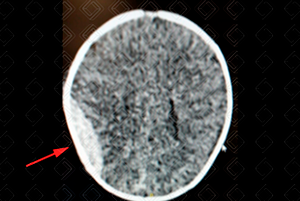

Texto alternativo para a imagem Figura 1. Créditos: Dra. Elazir Mota - Rio de Janeiro/RJ

Descrição das figuras 1 e 2: Tomografia de crânio revela um hematoma epidural biconvexo clássico à direita (seta vermelha). Há também um hematoma subgaleal laminar à esquerda (seta amarela). Abaixo (figura 3), foi realizada a reconstrução tridimensional do mesmo paciente, em busca de fraturas.

• Tomografia computadorizada do crânio (figuras 1, 2 e 3): Exam e de escolha no cenário de emergência por tratar-se de exame rápido e amplamente disponível. Co leção hiperdensa extra-axial e biconvexa . Deve-se procurar sempre por ar no interior do hematoma, que é um sinal de fratura associada do seio paranasal e mastoide, ou pelo sinal do redemoinho, uma heterogeneidade no interior do hematoma que sugere sangramento ativo. Sempre buscar por fraturas nas reconstruções tridimensionais (3D) e na janela óssea;